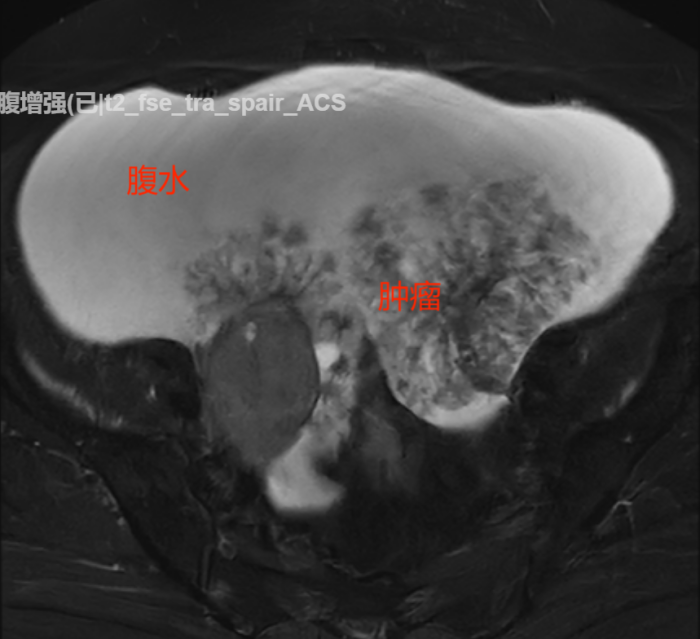

经过住院检查,医师发现何女士血清白蛋白值偏低,Ca125及HE4等卵巢癌指标异常升高。核磁共振结果进一步显示患者盆腔内有不规则团片影,其为肿瘤性病变或种植性病变的可能性较大,且患者腹腔、盆腔有大量积液,腹腔内脂肪间隙模糊,不排除外转移性病变的可能。

手术中,医疗团队成功抽出高达3000毫升的腹水,并完整切除了卵巢、输卵管、子宫以及所有盆底腹膜的多处转移病灶(包括多处膀胱及肠道浆膜层的种植病灶,较大直径为3cm),甚至精准切除了肾静脉水平的转移淋巴结,实现了对肿瘤细胞的全面“围剿”。术后,何女士在医护人员和家人的精心照料下,恢复情况良好,并顺利完成了后续化疗。